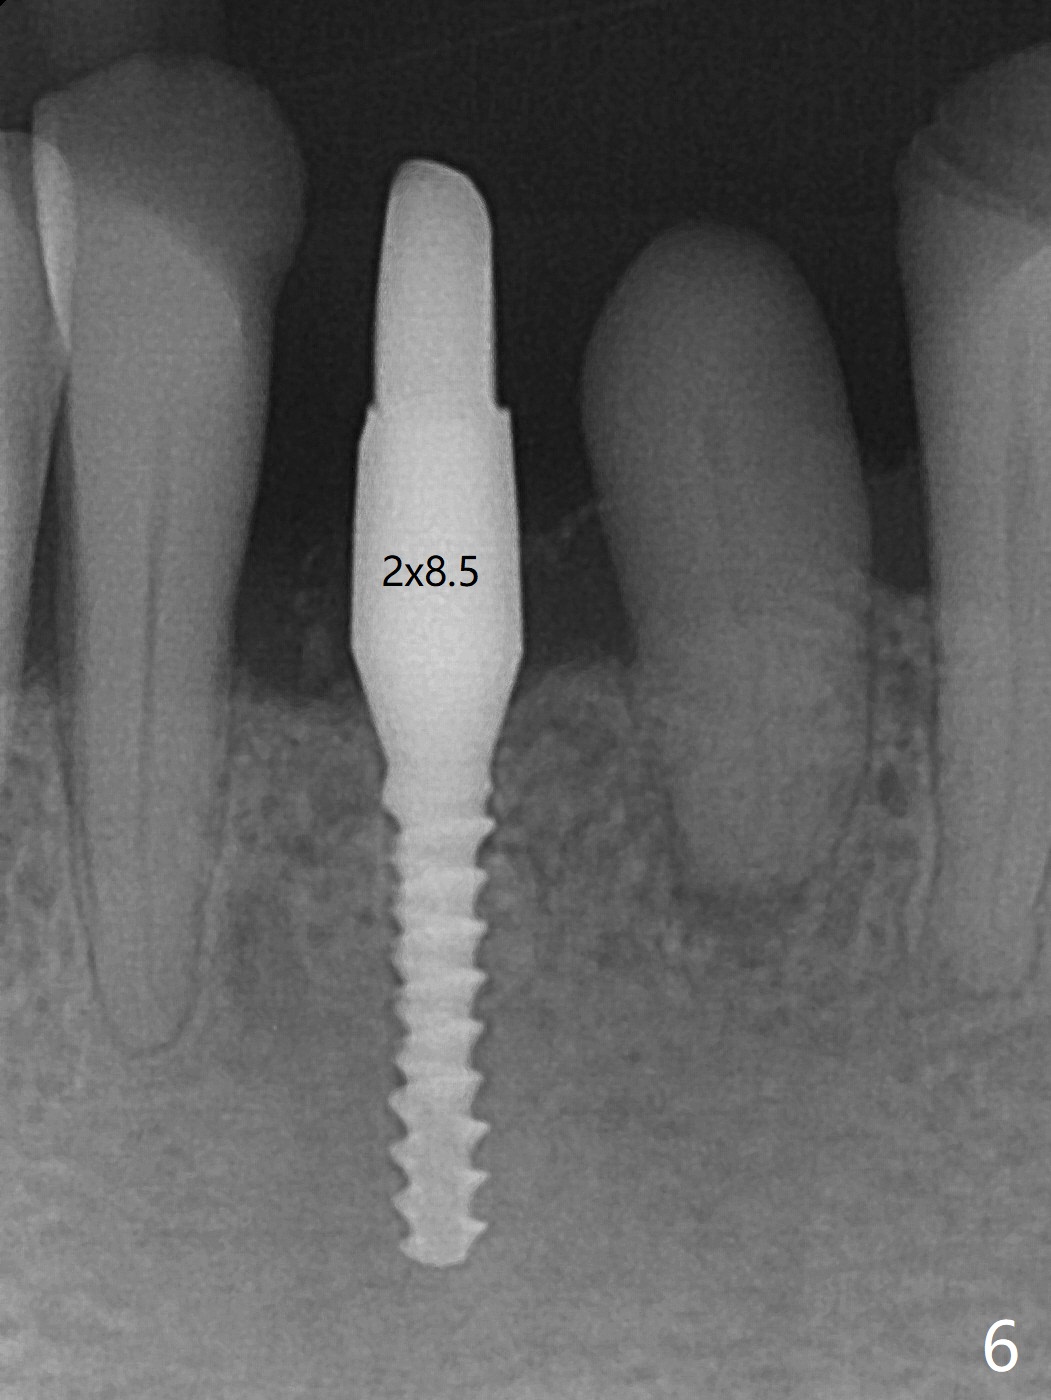

左下第一磨牙(#19)牙槽嵴狭窄,2.2毫米钻头完成导板钻洞后,舌侧骨板开始破裂(图一:<),打消牙槽嵴劈开术念头,放置2.5x8.5毫米一段式植体(图二(8.5毫米是最短植体)),好像离下齿槽神经管还有一定距离,适当植入深些(图四:箭头,15Ncm)。右下中切牙缺牙区牙槽嵴也十分狭窄(图四),最后不得不徒手植入2x8.5毫米植体(图五,六,25Ncm)。如果按设计植入2x12毫米植体,颊侧,或者舌侧骨板更容易穿孔。术后3.5月牙槽嵴下降(图七:箭头),可能术中那里压力太大,今后牙槽嵴钻洞要大。24号牙根尖阴影(图七),完成根管治疗(图八)。19牙位牙槽嵴吸收也严重(图九)。其实术后4个月19牙位牙槽嵴吸收并不严重(图十一)。